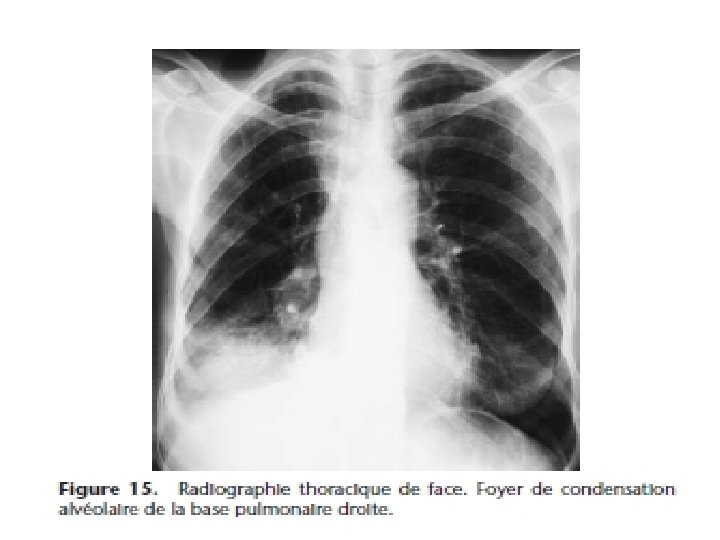

Kyste hydatique du poumon • Evolution radio-clinique 06 stades successifs: 1) Kyste sain. Asymptomatique de découverte fortuite (stade exclusivement radiologique)= opacité ronde, nettement limitée, en « boulet de canon » , dans un parenchyme sain, profil, opacité ovalaire « en ballon de rugby » , signe de NEMENOFF en radioscopie

2) Kyste malade ou kyste flétri. Stade clinique= expectoration hémoptoïque, peu abondante; et RX= opacité ronde, surmontée à son pôle supérieur du classique ménisque gazeux 3) Vomique: stade exclusivement clinique; rejet brutal de la vomique (parfois dramatique s’accompagnant de choc anaphylactique) ou vomique fractionnée